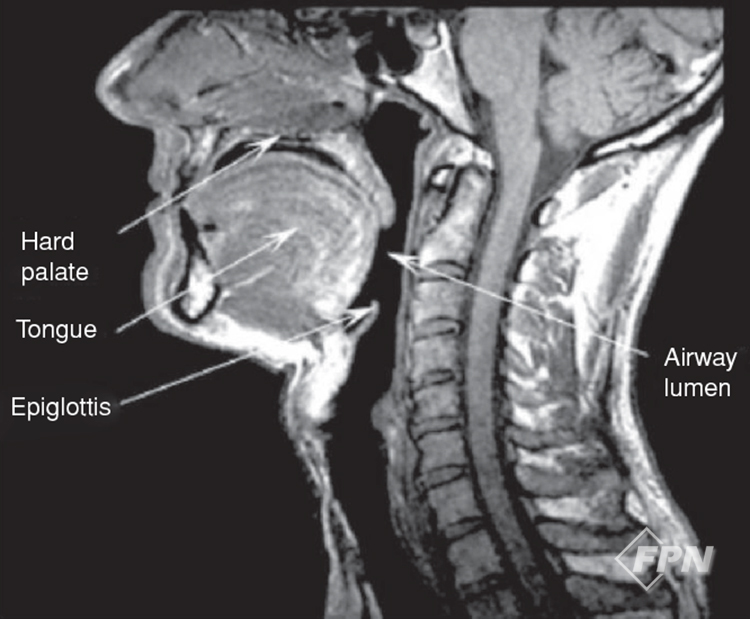

뇌 손상 초기 의식변화는 호흡 능력 소실과 혀의 처짐(이완)으로 이어지는데 처진 혀 근육은 [그림 1]과 같이 상기도를 막아 더욱 심한 저산소 혈증 상태를 만든다.

▲ [그림 1] 의식변화에 따른 혀 근육 이완에 의한 기도의 협착